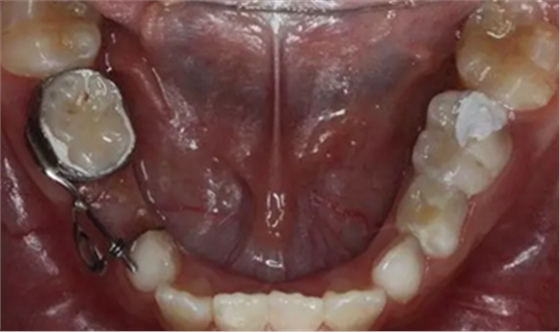

36、放回模型試合,合面觀

37、放回模型試合,頰面觀

40、加力后,重新就位合面觀

44、8周后復(fù)診間隙推開,自動變換為間隙保持器